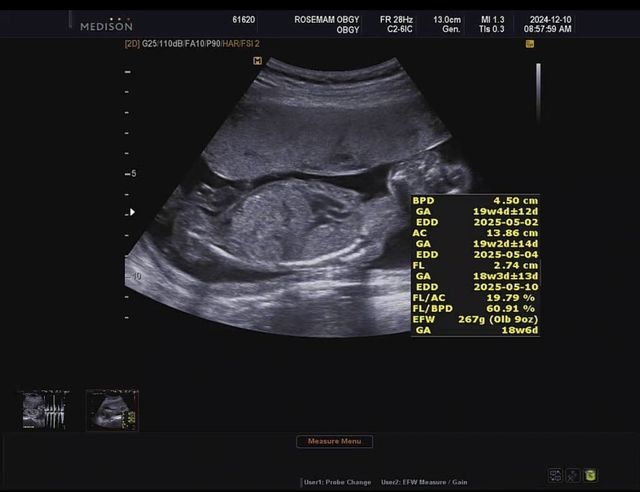

18주 된 아들램 입니다 ㅎㅎ

꼬물거리는데 너무 기엽다

내년 5월 출산예정 건강히 잘 컸으면 좋겠다!